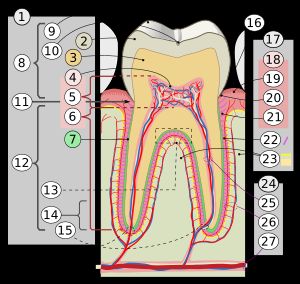

근관 치료는 치아 내부의 치수(치아 신경 및 혈관)에 발생한 문제로 인해 손상되거나 감염된 치아를 치료하는 치과 시술이다. 치아의 검사 및 진단을 통해 치료 계획을 세우고, 감염된 치수를 제거하고 근관을 소독 및 충전하는 과정을 거친다. 근관 치료 중에는 치아 천공, 기구 파절 등 사고가 발생할 수 있으며, 치료 후에는 치아 변색이나 재감염의 위험이 있다. 근관 치료는 치아를 보존하는 데 효과적이며, 실패 시 재치료나 외과적 치료, 발치 등의 추가적인 치료가 필요할 수 있다.

근관 치료를 시행하기 전에는 치수와 주변 치근단 조직에 대한 정확한 진단이 필요하다. 이를 통해 근관 치료 전문의는 치아와 주변 조직을 보존하고 수명을 연장할 수 있는 가장 적절한 치료 옵션을 선택할 수 있다. 비가역성 치수염의 치료 옵션에는 치아 발치 또는 치수 제거가 있다. 부분 치수 절단술(치수 절제술)은 개방된 치근단공을 가진 치아에서 치수를 보존하기 위한 최선의 치료법이다.[8]

만약 치아가 충치, 균열 등으로 인해 미래 감염이 매우 가능하거나 불가피하다고 판단되는 경우, 그러한 감염을 예방하기 위해 치수 절제술(치수 조직 제거)을 권장한다. 일반적으로 치아 내부 및/또는 아래에 어느 정도의 염증 및/또는 감염이 이미 존재한다. 감염을 치료하고 치아를 살리기 위해 치과 의사는 치수강에 구멍을 뚫고 감염된 치수를 제거한다. 이후 치수강과 치근관에서 세균을 제거하기 위해 효과적인 방부제와 소독제를 사용한다.[10] 연조직은 엔진 구동 회전 파일로 치근관에서 드릴로 제거하거나, H 파일 및 K 파일로 알려진 바늘 모양의 긴 수동 기구를 사용하여 제거한다.

치료를 계획하기 위해서는 해당 치아의 구강 내 중요성과 예후 및 근관에 대한 세심한 관찰이 필요하다. 고려해야 할 요소에는 심한 만곡근관, 치주염, 교합, 치아파절, 석회화변성, 폐쇄근관, 수복처치의 가능성, 복잡한 근관형태를 가지고 있는 치아 등이 있다.치수 치료를 실시하기 전에 치수 및 주변의 치근 첨단 조직에 대한 정확한 진단이 필요하다. 이 진단을 통해 치수 치료 전문의는 가장 적절한 치료를 선택할 수 있으며, 치아 및 주변 조직을 보존하고 장기간 유지할 수 있게 된다. 불가역적인 염증을 일으킨 치수의 치료는 발치 또는 발수 처치(근관 치료의 방법) 중 하나를 선택한다.

치아가 충치, 균열 등으로 심하게 손상되어 있고, 장래의 감염이 일어날 것 같거나 피할 수 없다고 생각되는 경우, 이러한 감염을 방지하기 위한 치수 절제술(치수 조직의 제거)이 권장된다. 통상적으로, 어느 정도의 염증 또는 감염이 치아의 내부 또는 하부에 이미 존재한다. 감염을 치료하고 치아를 보존하기 위해, 치과의는 치수강에 구멍을 뚫어 감염된 치수를 제거한 다음, 파일(또는 리머)이라고 알려진 긴 바늘 모양의 기구로 근관에서 신경을 적출한다.

근관장(working length)이란 근관 치료의 작업 길이를 뜻하며 근관 치료의 범위를 결정하는 기준이 된다. 근관장은 치아의 교두정(cusp tip)에서 근단공(apical foramen)의 가장 좁은 부위까지의 거리를 말하며, 근관장을 본래의 길이보다 짧게 측정시 나머지 부분의 세균을 제거하지 못하고, 길게 측정시 기구가 근관의 끝 이상을 넘어가 치주조직에 손상이 가해진다.[133]